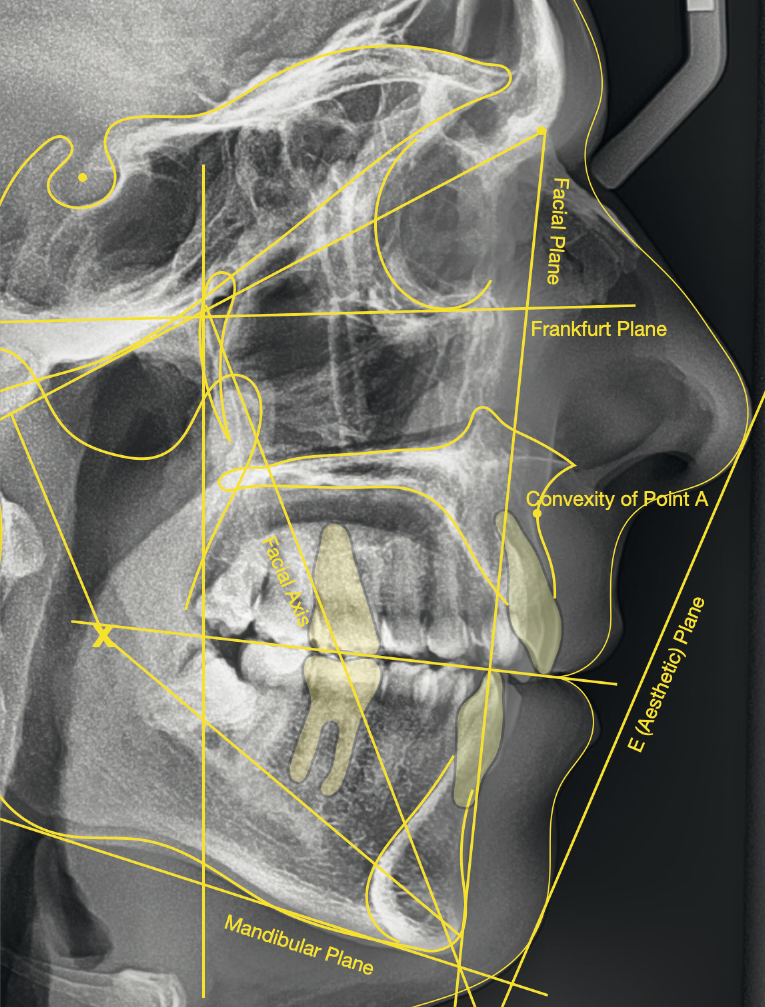

The cephalometric analysis showed a skeletal Class II malocclusion (convexity of Point A: 4.9 mm), a slightly retruded chin position (facial depth: 78.1°) and a skeletal open bite tendency (lower facial height: 53.19°; facial axis: 80.58°; Fig. 9). The mandibular incisors were lingually tipped (Li–APog: 9.3°) and retruded (Li–APog: 1.55 mm), and there was an increased inter-incisal angle of 142.9°.

Treatment results

The post-treatment extra-oral photographs showed the improvement of the smile aesthetics (Figs. 51–58). A solid bilateral Class I occlusion was achieved with normal overjet and overbite. The dental arches were well aligned and levelled, and even the severe rotation of the mandibular left second premolar was corrected with aligners only. The post-treatment cephalometric evaluation (Fig. 59) showed an improvement in the anteroposterior position of the mandibular incisors (Li–APog: 2.21 mm) while maintaining the facial height (lower facial height: 53.12°; facial axis: 83.96°; Table 1).